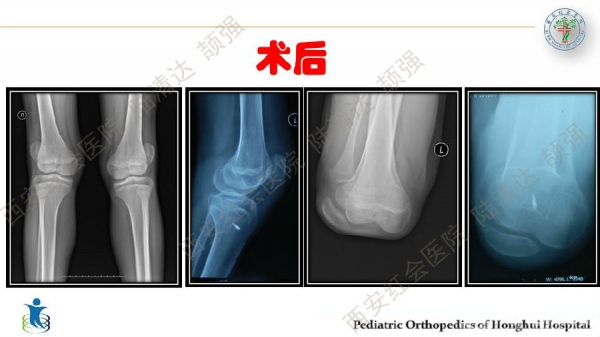

习惯性髌骨脱位,多见于儿童,女性多于男性。临床表现主要为行走步态难看、下肢无力、易摔跤等,而反复摔跤的病史常是患者就诊的主诉。其病理特点主要膝关节内外侧伸肌肌群不平衡及局部结构发育异常,表现为:股外侧肌及膝外侧软组织挛缩,髌韧带附着点偏外,股内侧肌群萎缩无力及MPFL发育不良,髌股关节滑车发育不良及膝外翻畸形等。习惯性髌骨脱位的治疗,建议早发现早治疗。不仅能有效解决脱位问题,还可避免继发畸形。如治疗延误,可出现髋、膝关节继发屈曲、腰前凸加大等畸形。甚至膝关节骨性关节炎,影响工作与生活。